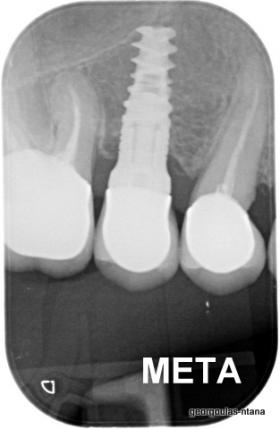

ΟΛΙΚΗ ΑΠΟΚΑΤΑΣΤΑΣΗ ΑΝΩ ΓΝΑΘΟΥ

Η ασθενής ήταν δυσαρεστημένη από την εμφάνιση των άνω δοντιών της. Ήθελε τα δόντια της να αποκτήσουν ομοιόμορφο, πιο λευκό χρώμα κ να αποκτήσει ένα πιο αρμονικό χαμόγελο με φυσική εμφάνιση. Λόγω των εκτεταμένων εμφράξεων σύνθετης ρητίνης στα πρόσθια δόντια, των εμφράξεων αμαλγάματος στα πίσω αριστερά δόντια αλλά και της υπάρχουσας γέφυρας στα πίσω δεξιά δόντια, και σε συνδυασμό με την επιθυμία της ασθενούς για φυσικό αποτέλεσμα αποφασίστηκε η τοποθέτηση ολοκεραμικών στεφανών στα δόντια της άνω γνάθου. Στη θέση του δεύτερου προγομφίου δεξιά τοποθετήθηκε εμφύτευμα. Πραγματοποιήθηκε περιοδοντική θεραπεία, ενδοδοντικές θεραπείες (απονευρώσεις) κ τοποθετήθηκαν ενδορριζικοί άξονες υαλονημάτων  όπου κρίθηκε απαραίτητο. Σε όλη τη διάρκεια της θεραπείας η ασθενής ήταν καλυμμένη αισθητικά κ λειτουργικά με προσωρινές αποκαταστάσεις.